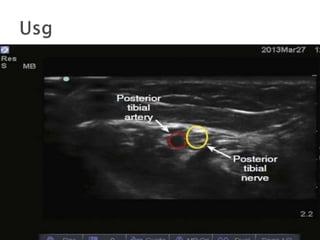

1. posterior tibial

10. The posterior tibial artery is palpated, and a 25-gauge, 3-cm needle is inserted posterolateral to the artery at the level of the medial malleolus